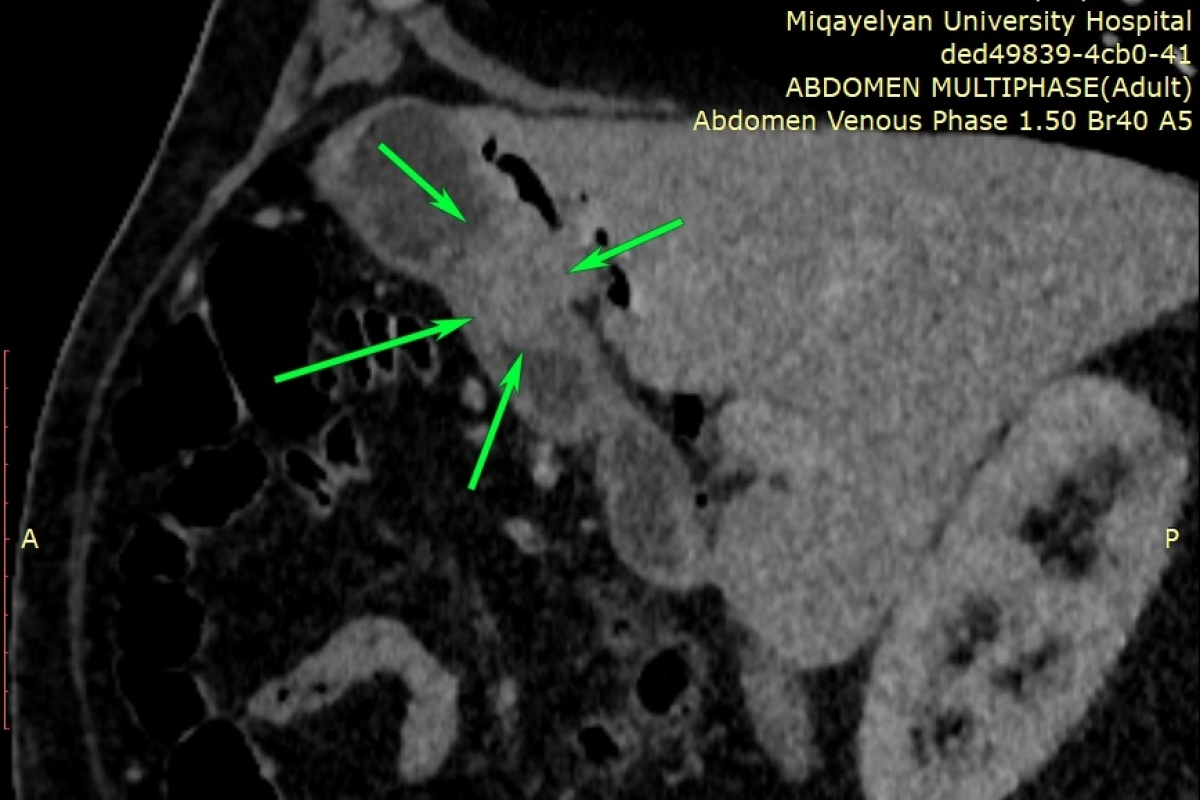

Էզոֆագոգաստրոդուոդենոսկոպիայի ժամանակ հայտնաբերվել է ստամոքսի առաջային պատի ուռուցք, որը տեղակայված էր ստամոքսաելքի շրջանում (ծառայության ղեկավար՝ Կարեն Մանուկյան): Կատարվել է նաև համակարգչային շերտագրություն կոնտրաստավորմամբ (ծառայության ղեկավար՝ Լևոն Դավթյան), որը հայտնաբերել է նշված հատվածում հստակ եզրերով ներպատային ուռուցք: